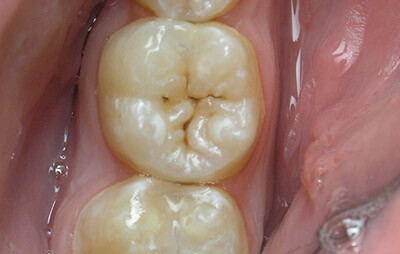

Поверхностный кариес

Стоит помнить о том, что своевременное обращение к специалисту может сохранить ваши зубы, а также избежать неприятных последствий заболевания. Поверхностный кариес являет собой заболевание зубной эмали, которая поражается вплоть до эмалево-дентинного основания. Его несвоевременное лечение может привести к таким осложнениям как пульпиты или периодонтиты, поэтому очень важно, чтобы лечение назначал компетентный специалист.

Кариес – это достаточно распространенное заболевание, которое провоцируется негативным воздействием внешних и внутренних факторов. Поверхностные повреждения возникают вследствие потери большого количества кальция, однако, эти нарушения пока еще не достигли дентина, поэтому важно как можно скорее его пролечить. Хотя заболевание не вызывает особого дискомфорта, в некоторых случаях оно проявляется такими симптомами:

— возникновение шероховатости и дефектов на эмали: их можно обнаружить благодаря рентгенографическому исследованию;